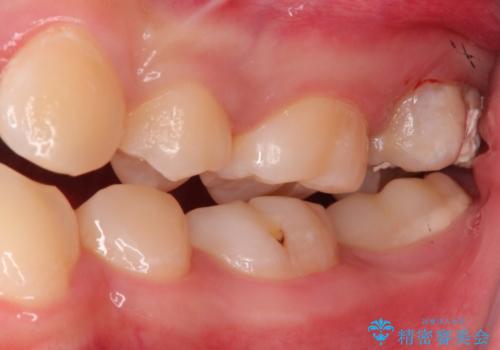

奥歯が痛い。ラバーダム使った治療がしたい。

- 他院にて奥歯の治療をしても痛みが引かずに、ラバーダムの存在を知り、無菌的な治療を行える病院を探して当院を受診されました。

根管治療~フルジルコニアクラウンにて修復しております。

治療前には打診、圧痛がありましたが治療後には症状が消失し、3ヶ月後のレントゲンでも透過像の縮小を認めています。

治療介入時、根管内部にはカリエスや異物が存在する状態でしたが適切な処置を行うことで症状を改善することができました。